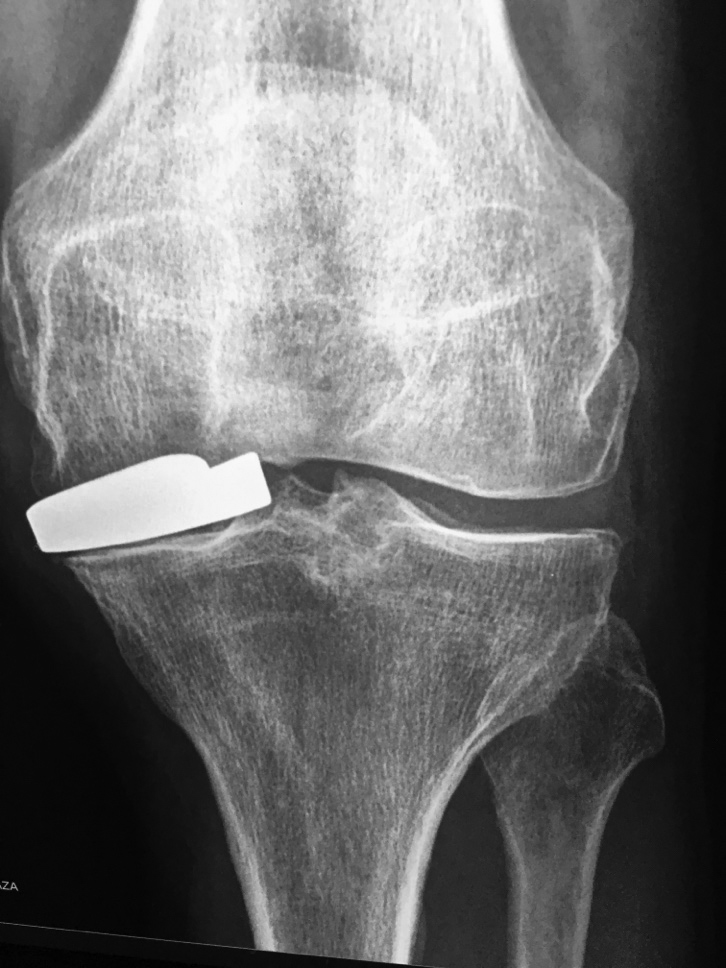

Left knee hemiarthroplasty (interpositional arthroplasty) Interference (Kurosaka) screw

Left knee interpositional arthroplasty

A metallic spacer sits on the medial tibial plateau. Image courtesy Brandon Runyan, MD. Interference (Kurosaka) screws are used to anchor anterior cruciate ligament graft in femoral and tibial metaphysis. Note the multiple osteochondromas (familial exostosis).